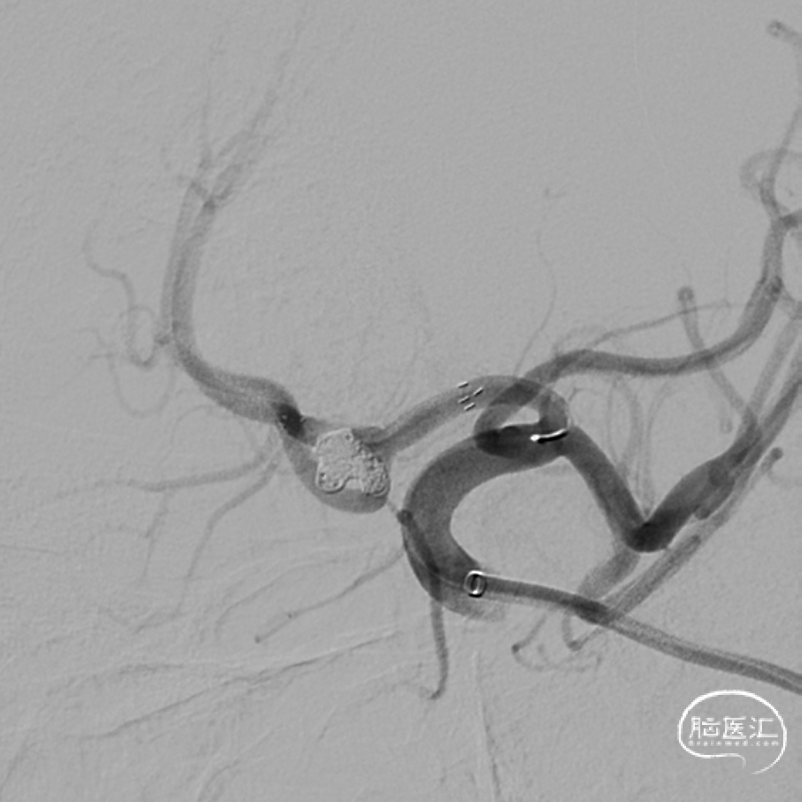

支架辅助下通过栓塞微导管向动脉瘤腔内送入Jasper®弹簧圈 4*10,一圈填塞两个子囊和瘤体。

后继续送入Jasper®弹簧圈若干,最终稳定致密栓塞。